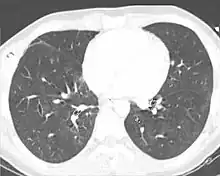

This CT scan, taken 22 days after pulmonary contusion with major chest trauma, shows that the contusion has completely resolved.[64]

Pulmonary contusion usually resolves itself[23] without causing permanent complications;[1] however it may also have long-term ill effects on respiratory function.[38][65] Most contusions resolve in five to seven days after the injury.[1] Signs detectable by radiography are usually gone within 10 days after the injury—when they are not, other conditions, such as pneumonia, are the likely cause.[27] Chronic lung disease correlates with the size of the contusion and can interfere with an individual's ability to return to work.[24] Fibrosis of the lungs can occur, resulting in dyspnea (shortness of breath), low blood oxygenation, and reduced functional residual capacity for as long as six years after the injury.[38] As late as four years post-injury, decreased functional residual capacity has been found in most pulmonary contusion patients studied.[43] During the six months after pulmonary contusion, up to 90% of people have difficulty breathing.[27][43] In some cases, dyspnea persists for an indefinite period.[7] Contusion can also permanently reduce the compliance of the lungs.[66]